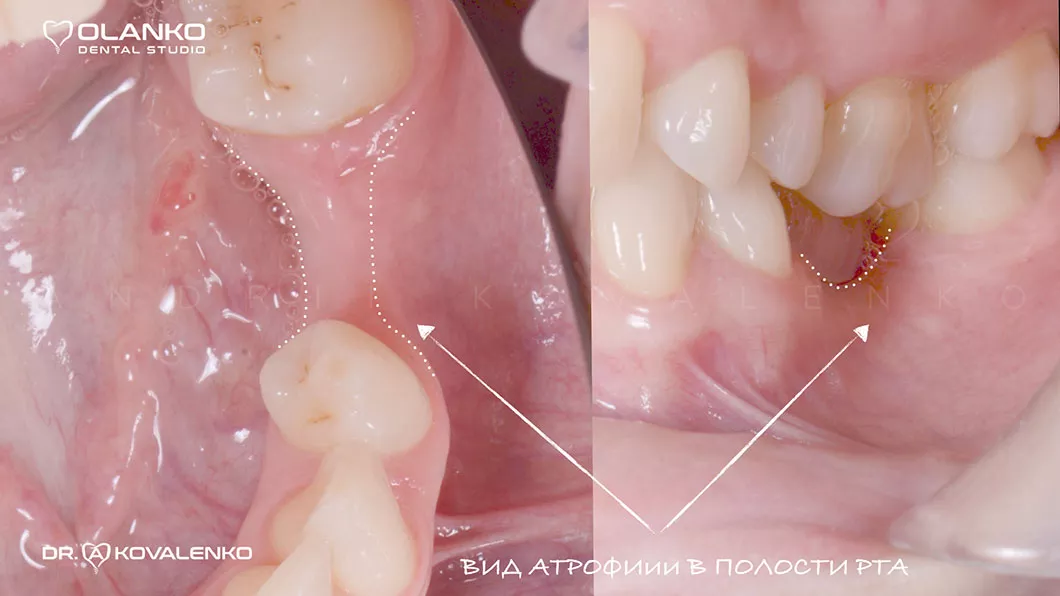

Атрофия — это прогрессирующая убыль костной ткани, которая сопровождается уменьшением ширины и высоты альвеолярного гребня. Развивается после удаления зуба и является самым распространённым препятствием для установки зубного имплантата.

Костная пластика – это хирургическая операция, которая позволяет восстановить объём челюстной кости, для будущей зубной имплантации, с помощью костной ткани, взятой в донорских зонах у пациента, или искусственного костнопластического материала, а также смеси костных материалов.

Операция костной пластики может выполнятся как самостоятельно, так и совместно с установкой зубного имплантата.